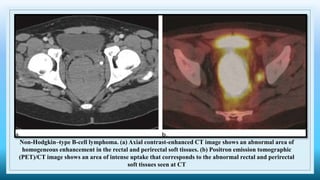

Non-Hodgkin–type B-cell lymphoma. (a) Axial contrast-enhanced CT image shows an abnormal area of

homogeneous enhancement in the rectal and perirectal soft tissues. (b) Positron emission tomographic

(PET)/CT image shows an area of intense uptake that corresponds to the abnormal rectal and perirectal

soft tissues seen at CT